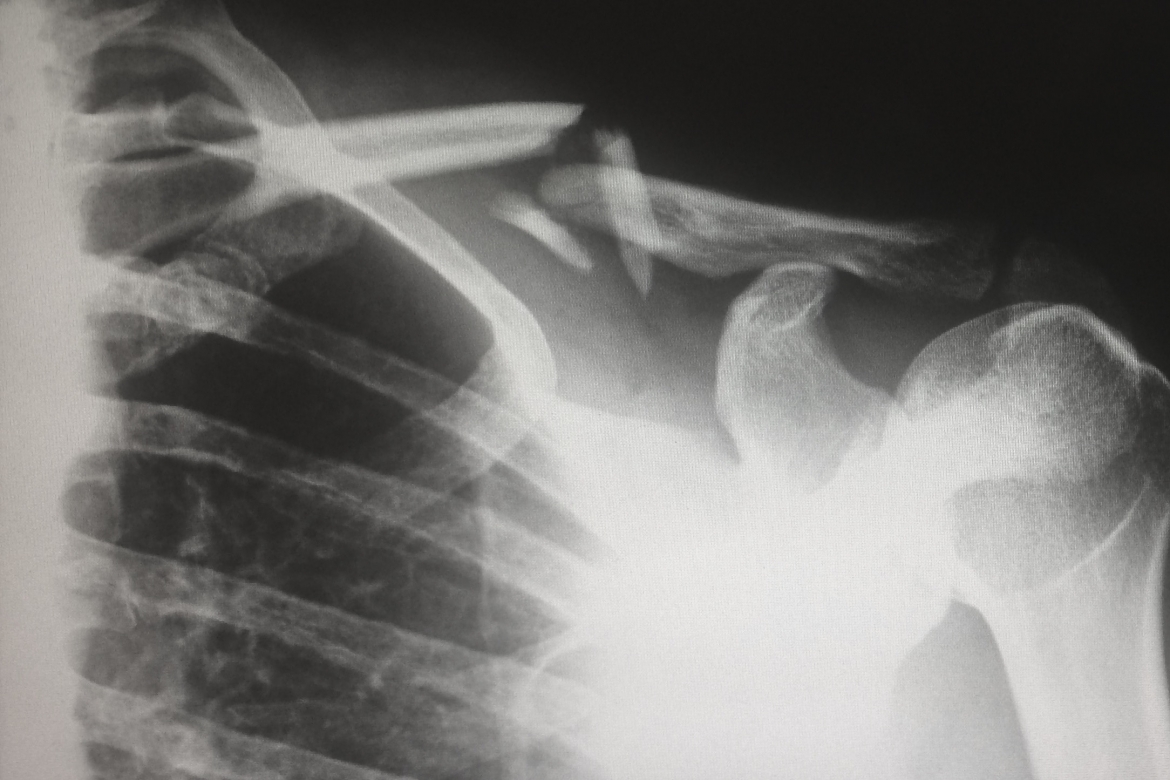

O processo de freeze-casting refere-se à uma técnica que explora o comportamento de solidificação altamente anisotrópico de um solvente (geralmente água) numa suspensão dispersa para modelar controladamente uma cerâmica porosa. A hidroxiapatita, por sua vez, é o principal constituinte mineral de ossos e dentes de vertebrados. O desenvolvimento de novos biomateriais macro-porosos para engenharia de tecido permite fornecer novos suportes para a regeneração óssea de um paciente em casos de fratura.